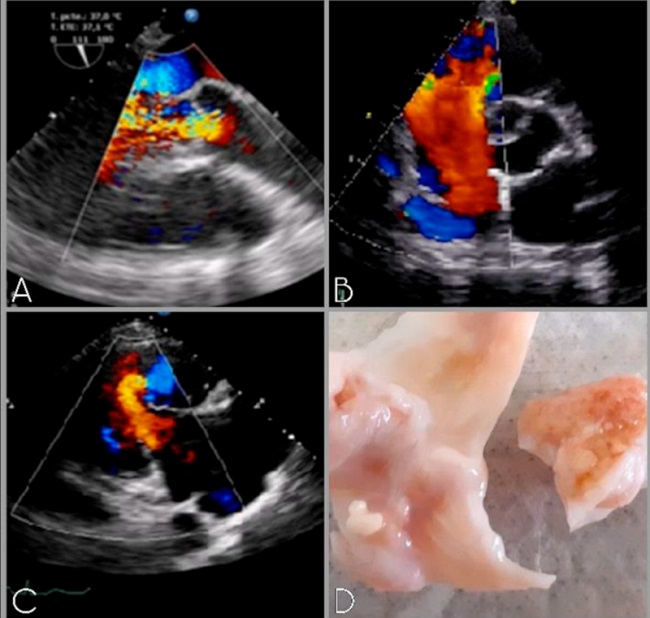

Paciente de sexo femenino de 71 años sin factores de riesgo cardiovascular, con antecedente de cáncer de mama tratado a los 50 años, que consulta por disnea progresiva y diagnóstico de tumor neuroendocrino en intestino delgado con múltiples metástasis hepáticas diagnosticado con tomografía con emisiones de positrones (PET). El ecocardiograma Doppler evidencia insuficiencia tricuspídea y pulmonar graves, con dilatación ventricular derecha y función biventricular conservada, y afectación valvular izquierda con insuficiencia aórtica grave (Imagen 1 A, B, C). Luego de la evaluación multidisciplinaria se decide resolución quirúrgica. Como hallazgo intraoperatorio las válvulas afectadas presentaban engrosamiento fibroso y retracción característicos de la enfermedad carcinoide (Imagen 1 D).

Se realiza cirugía de reemplazo valvular tricúspideo, pulmonar y aórtico (N31, N23 y N23 respectivamente) y puente aorto-coronario con vena safena a coronaria derecha por lesión diagnosticada en la cinecoronariografía preoperatoria. La paciente evoluciona satisfactoriamente sin complicaciones siendo egresada de la institución al décimo día postoperatorio. Actualmente lleva 3 años de sobrevida asintomática en seguimiento.